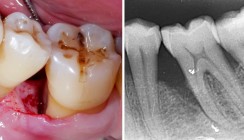

Die Patientin (ehemalige Raucherin) stand in den letzten Jahren unter erheblichem psychischem Stress. In dieser Zeit bemerkte sie eine deutliche Progression ihrer parodontalen Erkrankung. Sie hatte sich Monate zuvor einer nichtchirurgischen Parodontitistherapie sowie einer pa­rodontalen Lappenoperation im Bereich der Un­terkiefermolaren (46-47) unterzogen, die jedoch nur eine begrenzte Verbesserung gebracht hatten. Beim Sondieren wurde ein eitriger Ausfluss in den oberen Backenzähnen (17) festgestellt. Es zeigte sich generalisierte Plaque mit lokalisierten Zahnsteinablagerun­-gen. Die Pa­tientin war ansonsten allgemein gesund und hatte keine weiteren Beschwerden. Trotz der parodontalen Chirurgie in Regio 46 und 47 wurden lokalisiert erhöhte Sondierungstiefen von 6 bis 10 mm bei den Zähnen 17, 36-37 sowie 46-47 festgestellt. Inte­ressanterweise gab es keine Zahnbeweglichkeit außer Grad I bei Zahn 17. Zusätzlich wurde eine Furkationsbeteiligung Grad I bukkal an Zahn 17 beobachtet.

Ausgeprägter Knochenverlust in Molarenregionen

Periapikale Röntgenaufnahmen zeigten einen vertikalen/angulären Knochenverlust in den Regio­nen 16, 17, 36-37 und 46-47, der sich bis zum mittleren Drit­tel der Wurzeln erstreckte. Gemäß der Klassifikation der Parodontalerkrankungen von 2017 wurde eine lokalisierte Parodontitis – Sta­dium III (schwer), Grad C (schnelle Progression) diagnostiziert. Die Erkrankung war auf die Mola­renregionen mit Resttaschen > 6 mm begrenzt.